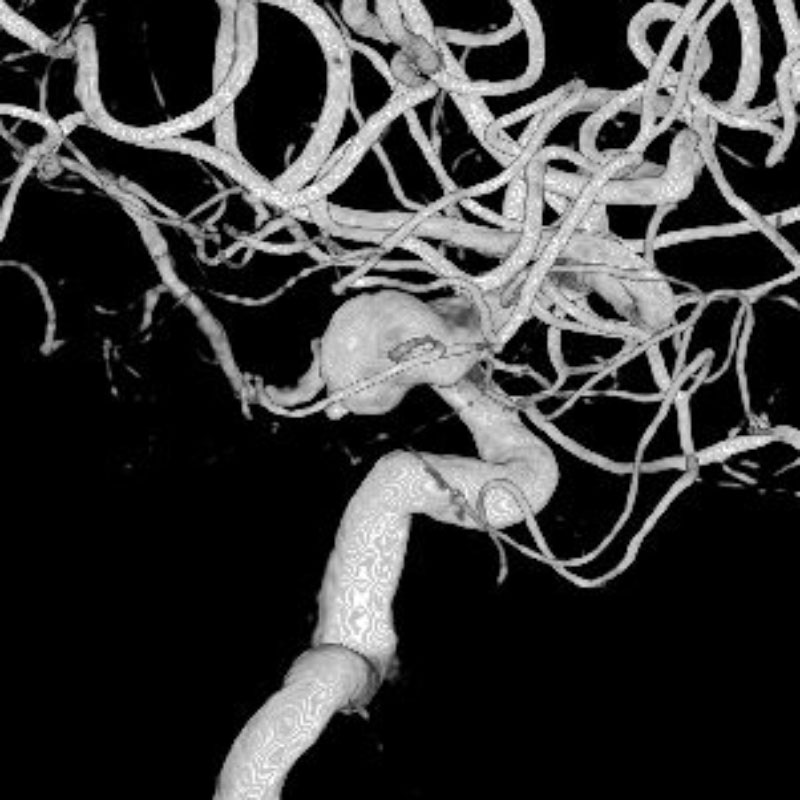

脳動脈瘤(Acom)

クリッピング術

松田/濵田/元永